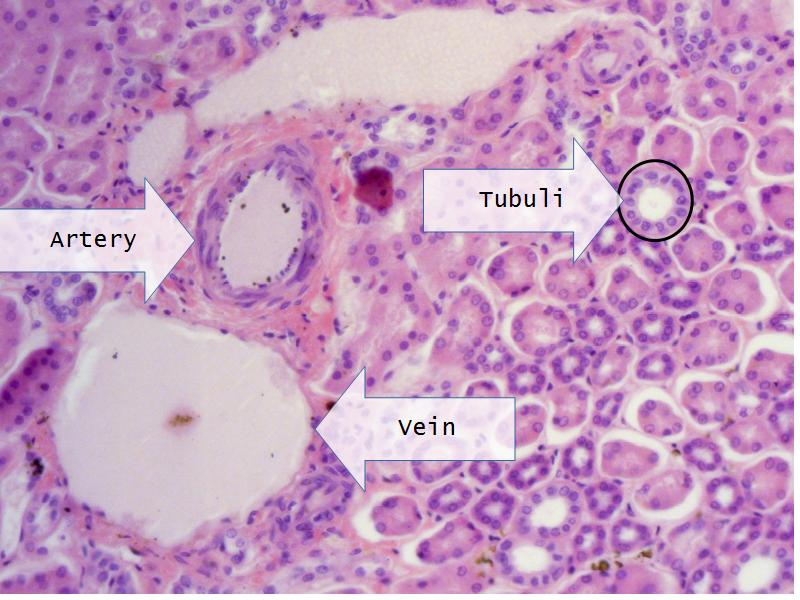

- Slide 76: Kidney